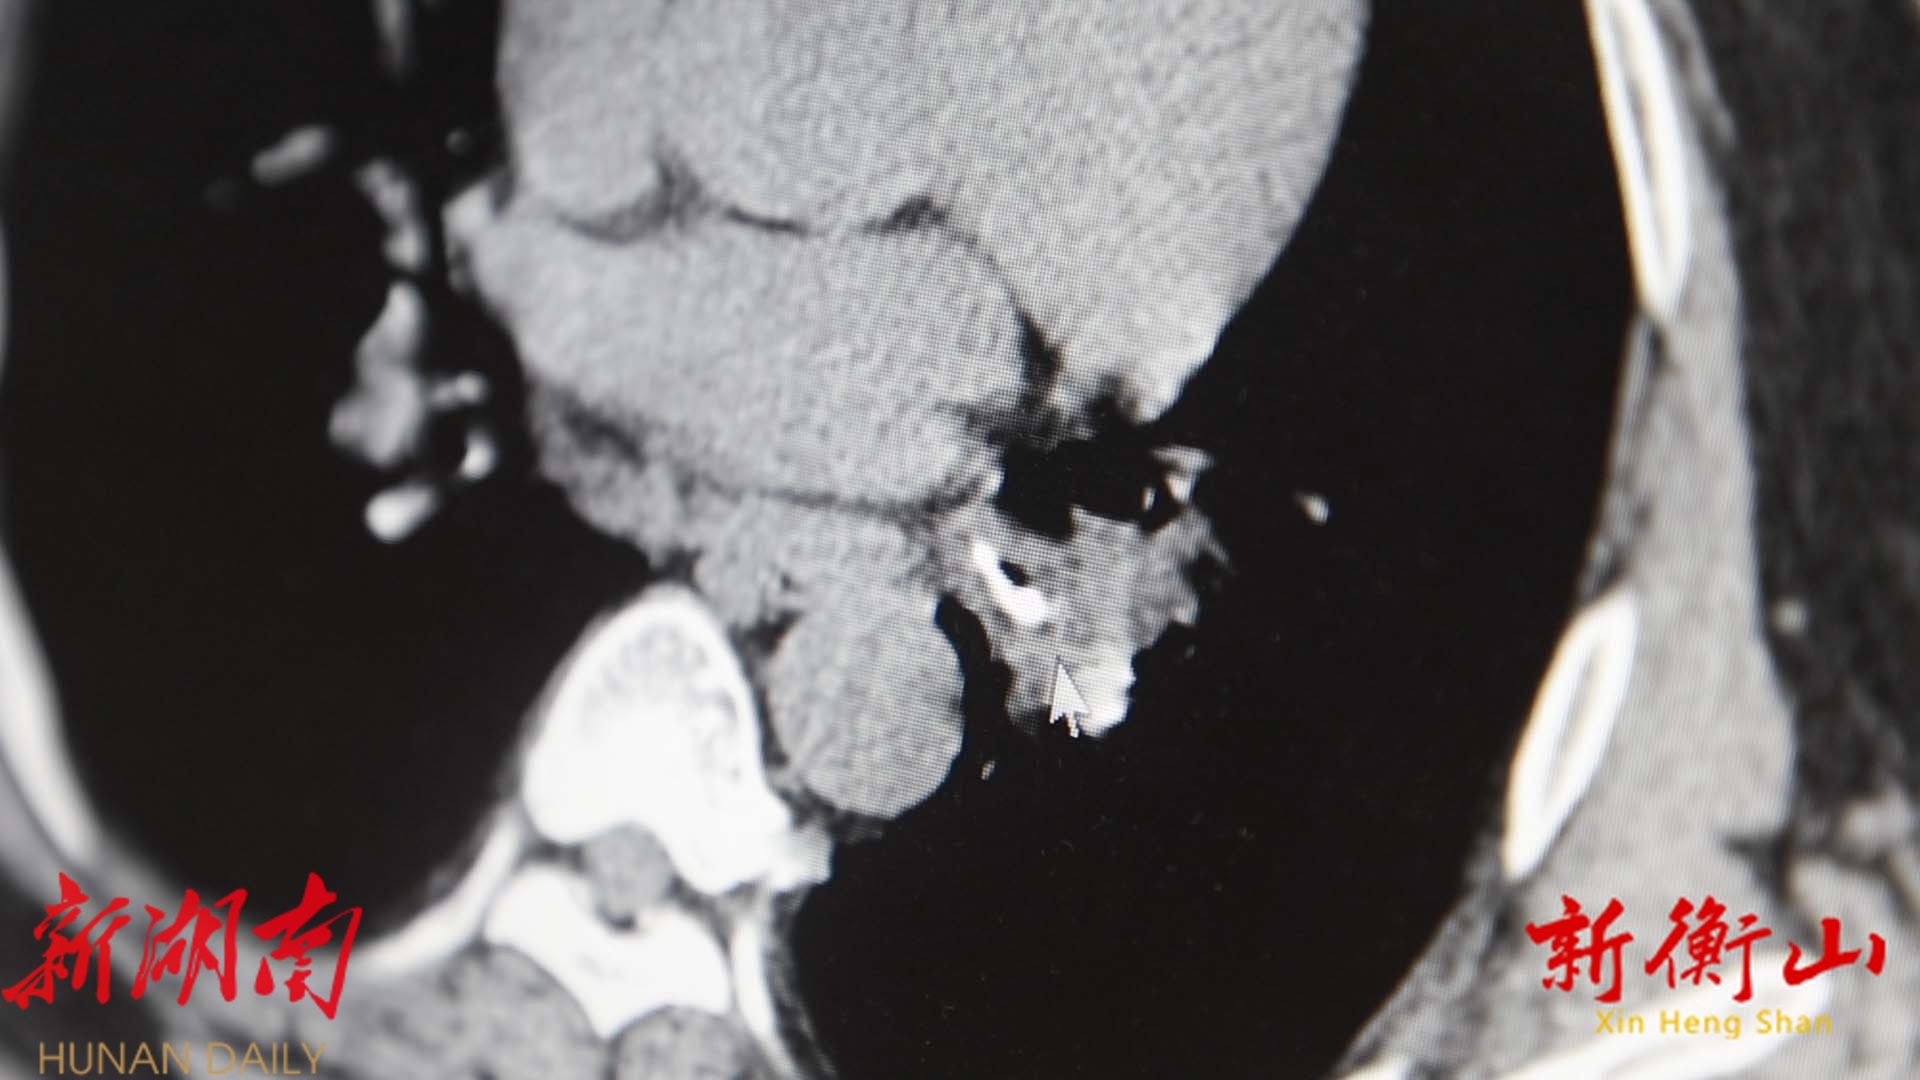

原来,市民康先生50年来一直反复咳嗽,进食时频繁出现恶心、呕吐等症状,起初,康先生及其家人以为是其体质弱导致,并未引起重视,也未曾前往医院系统就诊。但就在近期,康先生咳嗽症状突然加重,在县人民医院就诊进行CT检查后,发现其左侧支气管存在异物,肺部化脓性感染。随即,医院为其安排了支气管镜检查。

经过支气管镜检查后,医生发现,在康先生的气管内,卡着一枚指甲盖大小的铁片。康先生这才回忆起,自己年少时在玩耍过程中不慎误吞过一个小铁片,但由于当时医疗设备的限制,医生仅建议其食用韭菜促进异物排出再复查,因为当时不够重视,也没有复查过,导致这枚小小的铁片在其气管中“潜伏”近50年,成为引发他多年病痛的“罪魁祸首”。

“我们在CT上做了评估,是一个1.5乘以3厘米大小的异物,钳夹出来才发现是一个拇指大小的铁片。”衡山县人民医院呼吸与危重症医学科副主任医师刘东阳告诉记者。

确定异物位置后,呼吸与危重症医学科迅速为患者实施了“支气管镜下异物取出”,镜下清晰地发现了那枚藏匿已久的铁片,耗时40多分钟,这枚带着褐色钙化斑的近50年的小铁片被医生轻轻地夹了出来。